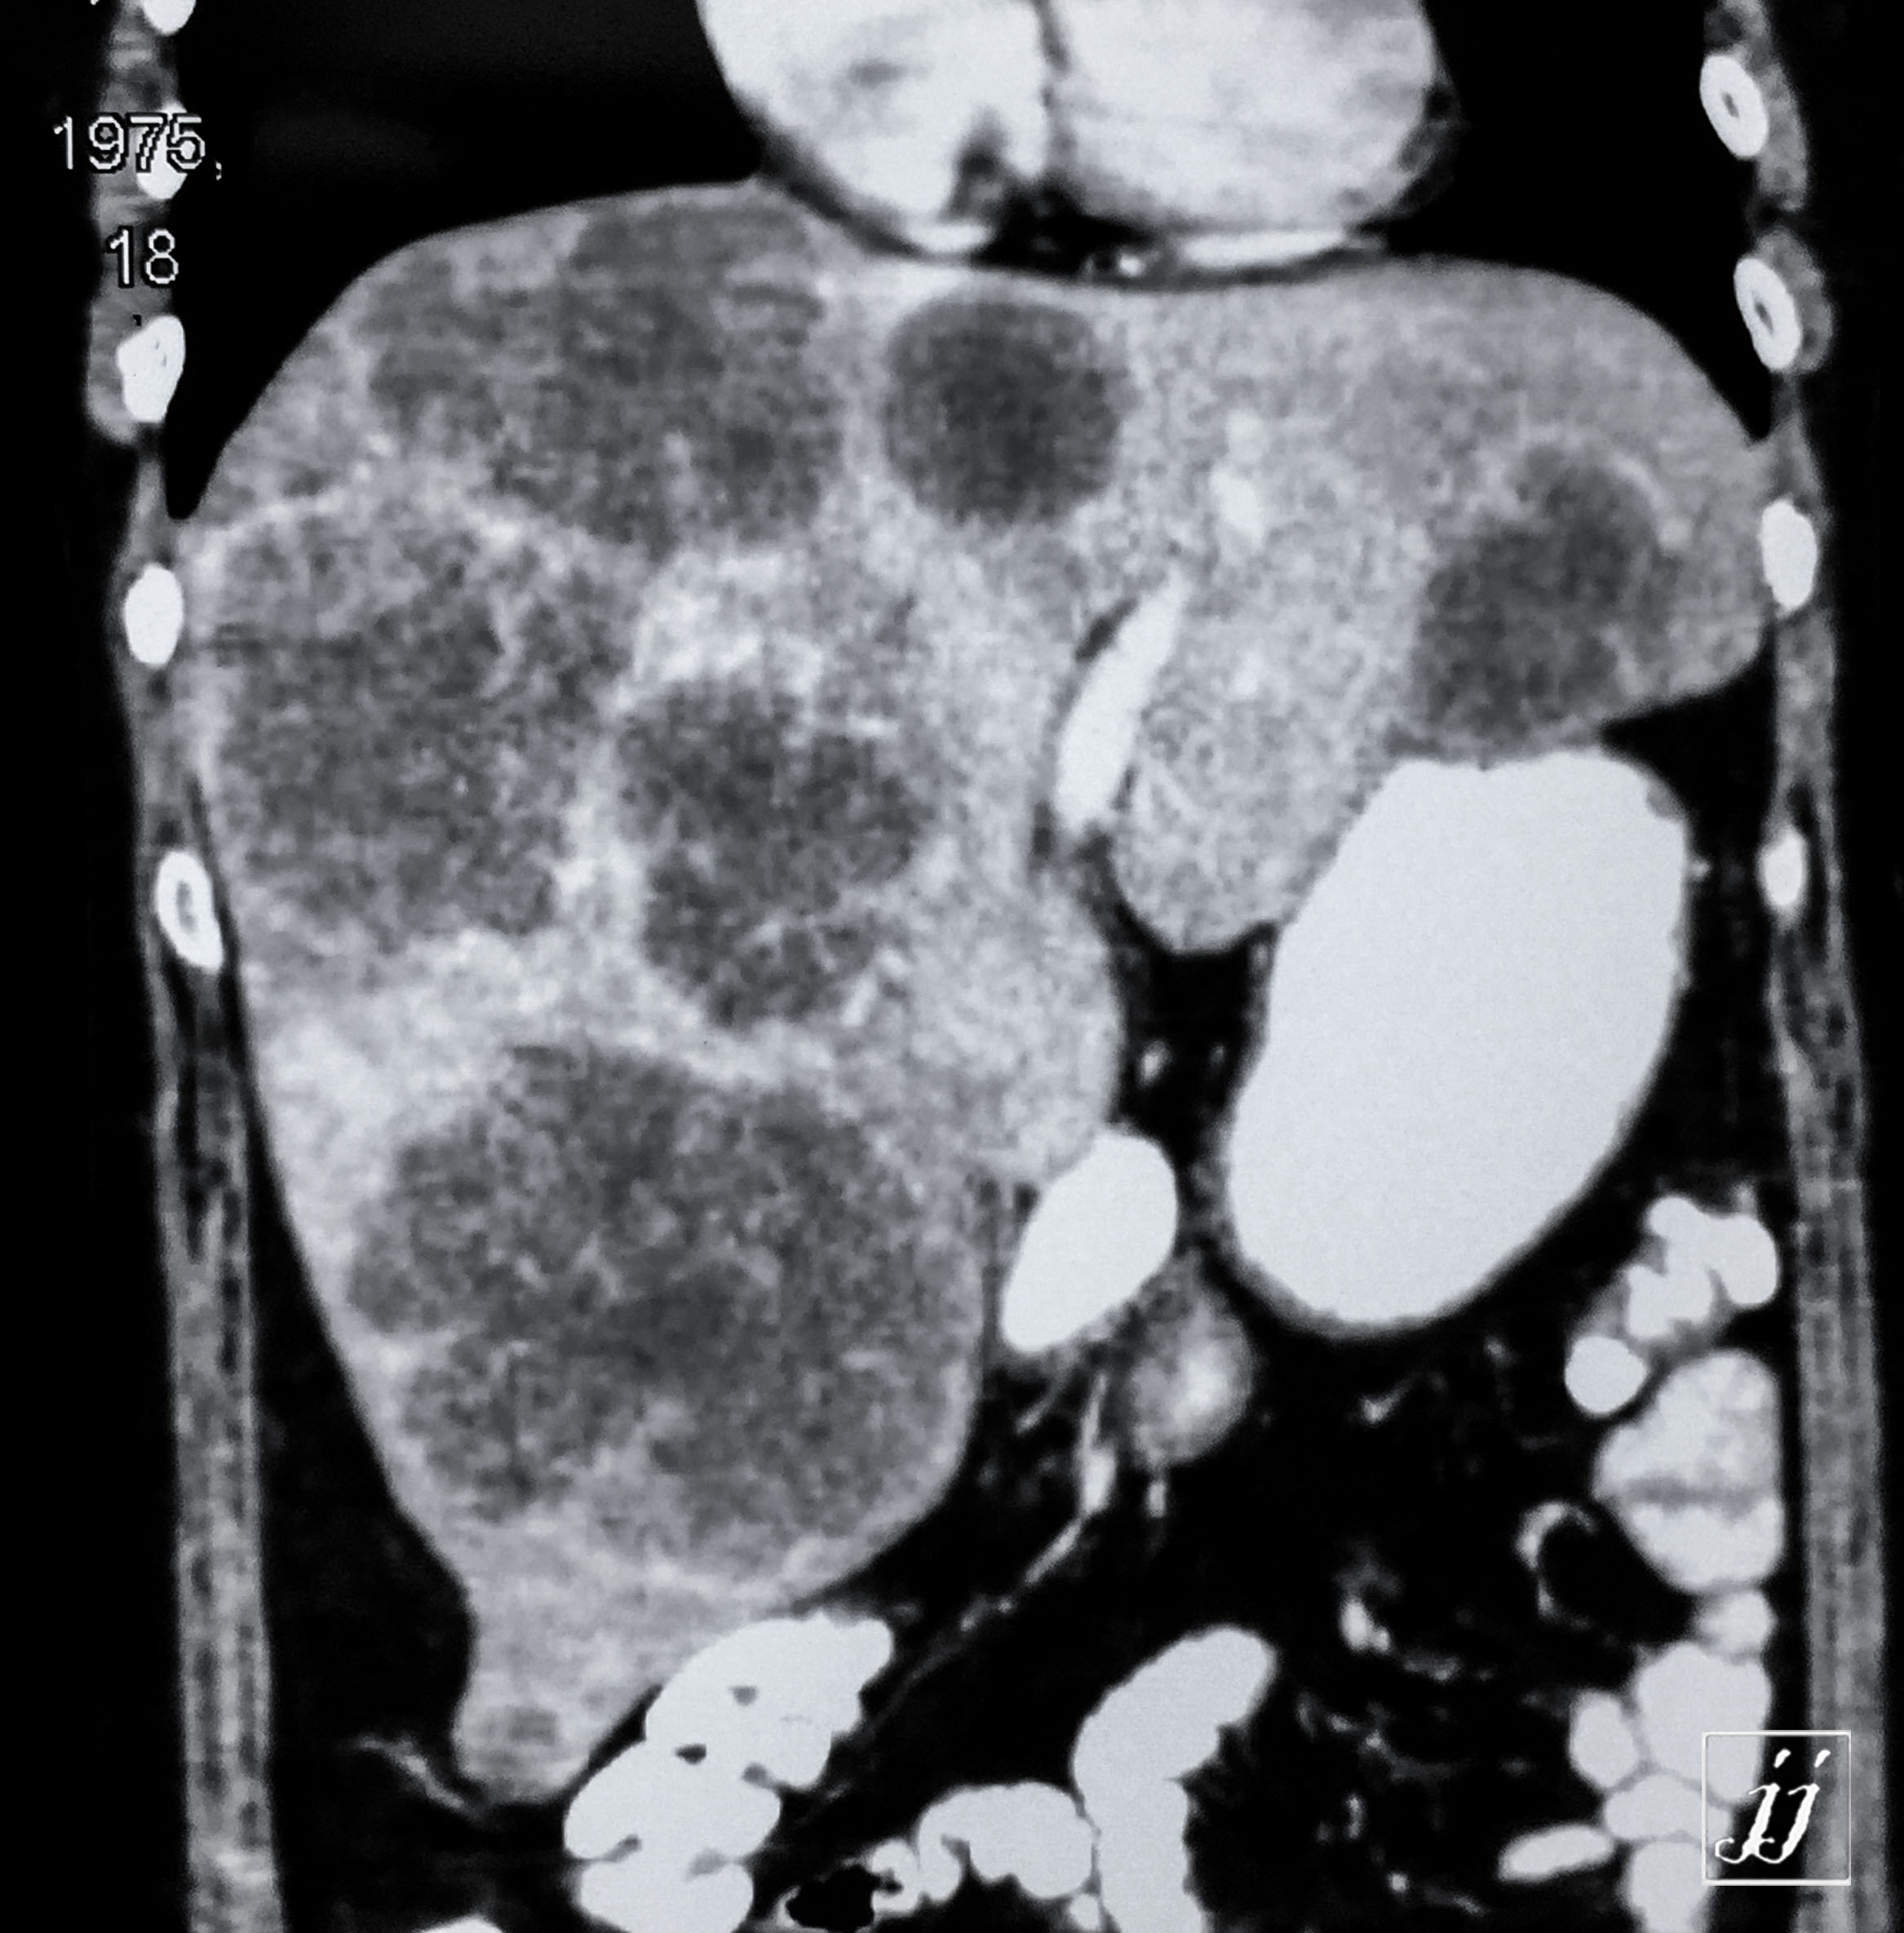

Abdomen- liver tumors and pancreas calcification vascular, gall bladder sedimentation, metastatic (13)